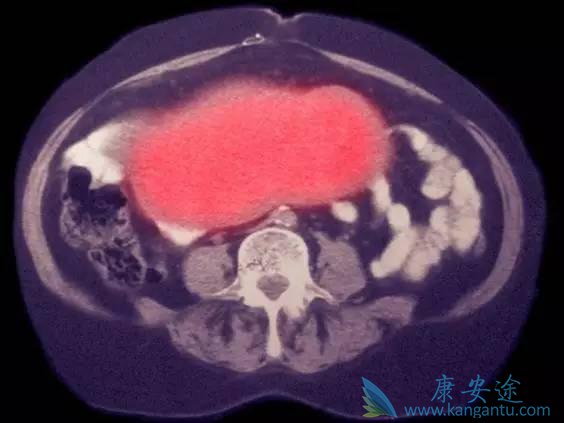

▲卵巢癌治疗效果不佳,跟发现时大部分病例都是晚期有关。(图片来源:independent)

卵巢癌是一种难治的疾病,在晚期阶段的预后很差。大约五分之一的卵巢癌妇女在确诊时肿瘤已经处于蔓延到全身并且无法治愈的阶段。根据国家癌症中心公布的统计数据显示,2015年中国有51200例新发卵巢癌,大约22500名妇女死于该疾病。